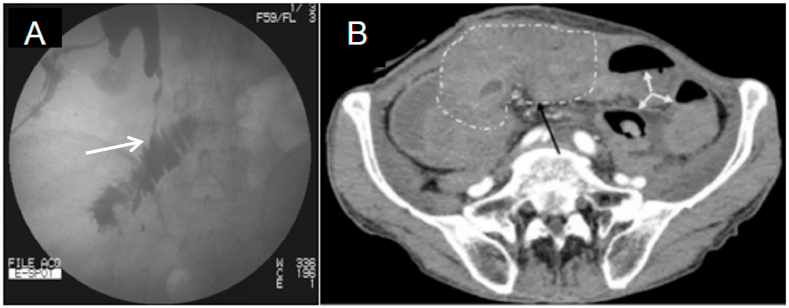

Fig. 2.

A:Antegrade pyelogram through the right nephrostomy tubes showed the passage of contrast media beyond the ureteropelvic tract to the ileum(white arrowheads).

B: CT scan of the pelvis shows intra-abdominal structure disorder and indistinct(black arrowheads), including obstruction, dilation(white arrowheads), and infection.